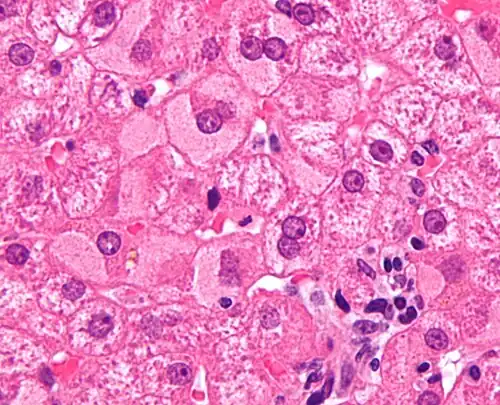

Ground glass hepatocytes -

A previously undiagnosed liver disease may become evident first after autopsy. Following are gross pathology images: